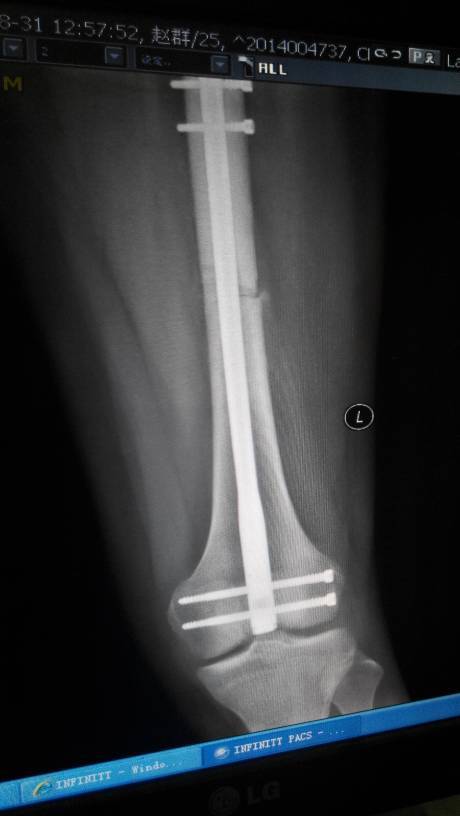

这个从X线片上来看,这个骨折处恢复还是比较好的,这个出现疼痛,是考虑骨折处的血液循环不畅,不通则痛所致,这个适当局部按摩,或者是用些活血通络的药物治疗,是会恢复好的。